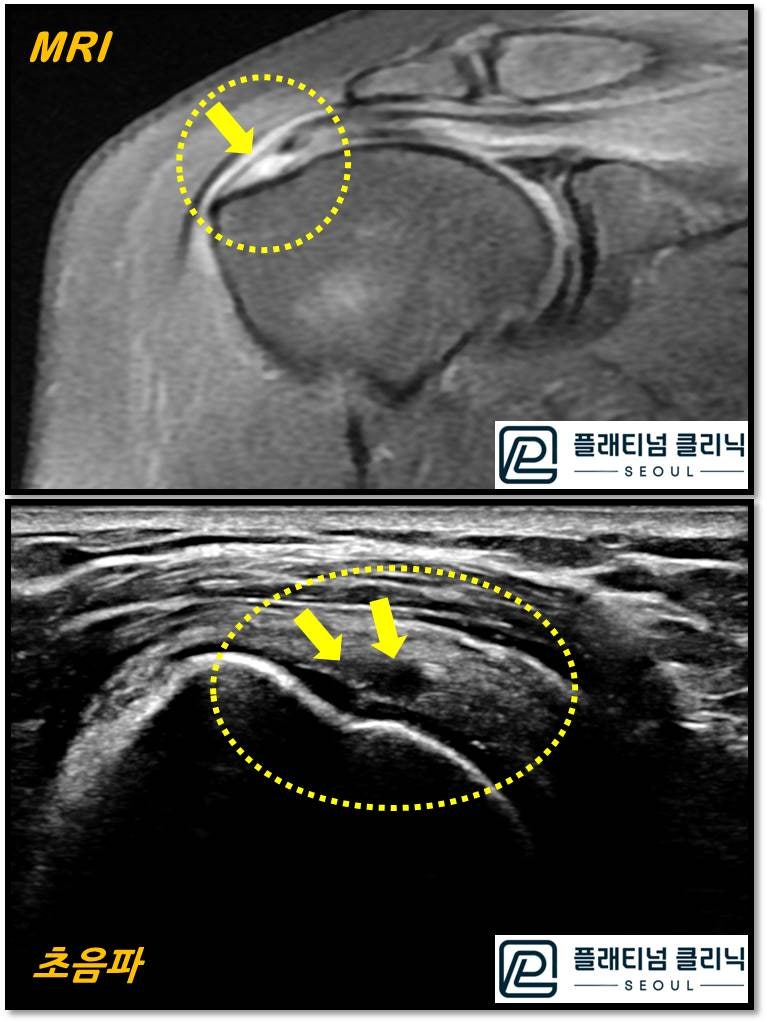

회전근개 파열에서 MRI 와 초음파를 비교한 사진입니다. 위의 사진이 MRI 이며 아래쪽에 있는 것이 초음파 사진입니다. 노란 원안에 화살표로 표시된 부위가 파열된 부위인데 MRI 에서는 힘줄이 검게 보이고 파열된 부위가 하얗게 보입니다. 초음파에서는 힘줄이 하얗게 보이고 파열된 부위가 검게 보입니다. 어떻게 보이시나요? 저는 초음파가 더 선명하고 크게 보입니다. 실제로 힘줄의 실질도 잘 관찰이 되고 근육이 방향도 잘 관찰됩니다. 물론 초음파를 오랜기간 봐 왔기 때문에 어느정도 숙련도가 있어서 더 잘보이는 것도 있을 겁니다.